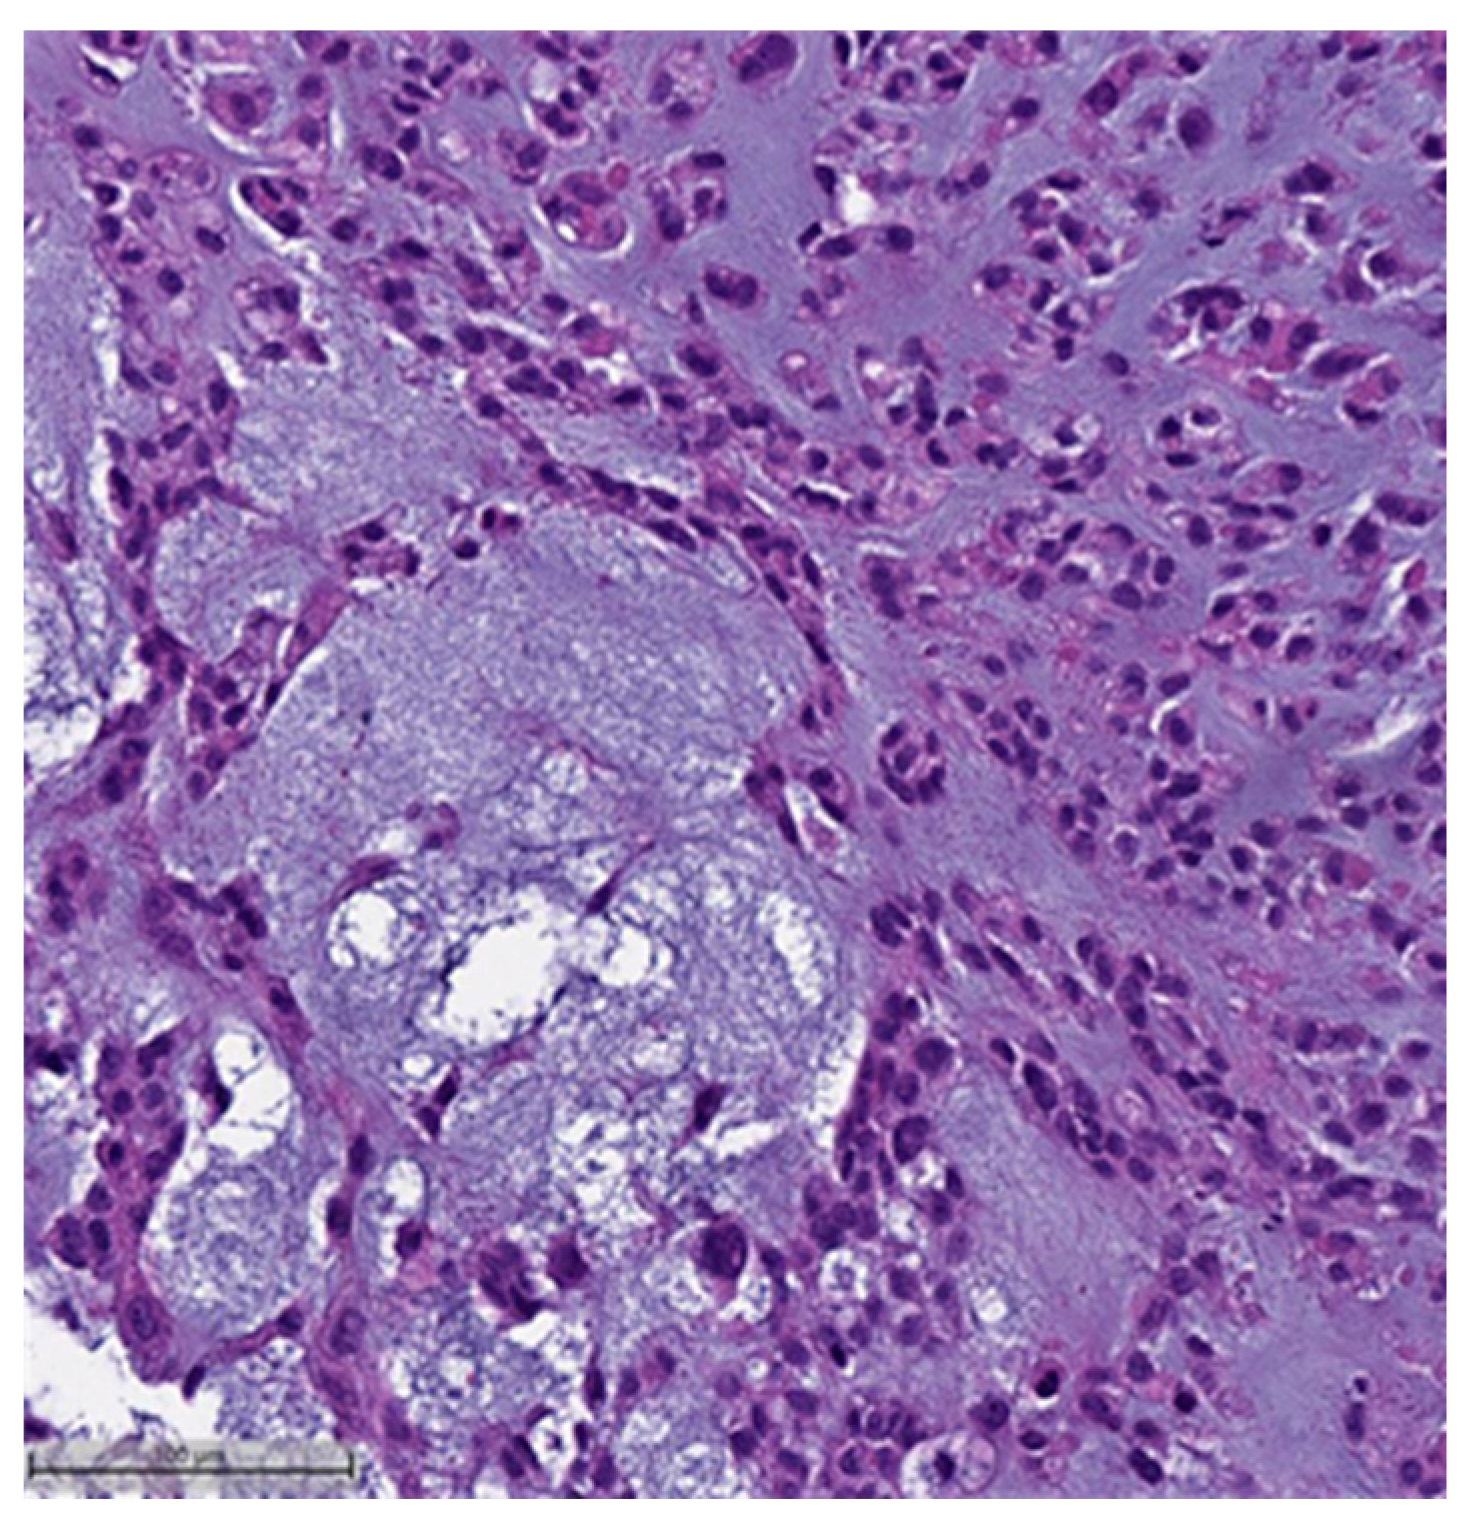

Figure 1. Squamous cell carcinoma component. This case also showed myxoid matrix areas (H&E, 20×).

Figure 2. Squamous cell carcinoma component (H&E, 20×).- Spindle cell carcinoma (SpCC) (Figure 3);